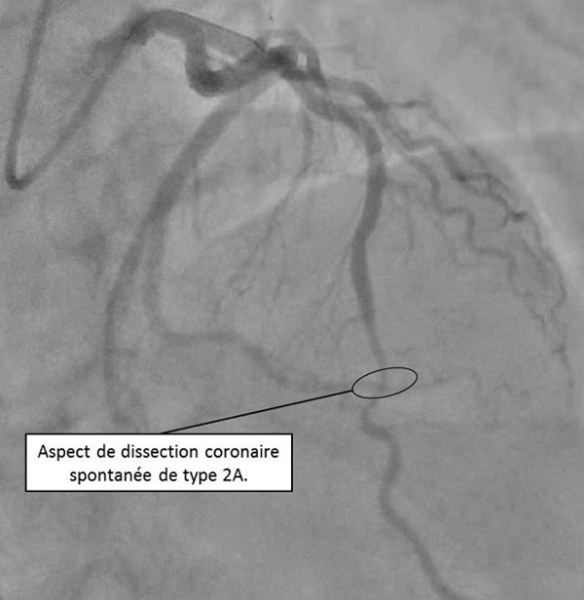

Figure 2 : Coronarographie : réseau coronaire gauche - incidence apicale (10/40)

La coronarographie met en évidence un réseau gauche dominant, non athéromateux, avec des artères plutôt « lisses », hormis sur l’incidence crâniale « 10°/40° » (pour 10° d’oblique antérieure droite et 40° de crânial) où l’on met en évidence une sténose d’allure significative de l’IVA distale, qui persiste après injection de dérivé nitré. Il existe une réduction de calibre homogène qui débute et qui se termine en regard de petites branches de bifurcation, avec un aspect dit de « phasme ». Le flux coronaire est préservé, TIMI 3. Il n’y a pas de thrombus visible sur cette coronarographie. Cet aspect évoque en premier lieu une dissection coronaire spontanée.

Figure 3B : Classification angiographique des dissections coronaires spontanées. Type 1 (A), Type 2A (B), Type 2B (C), Type 3 (D), Type 4 (E), intermédiaire entre Type1/2 (F).

- Type 1 : image classique en double lumière linéaire avec l’identification d’un flap radio transparent, fréquemment associé à une rétention de produit de contraste dans la fausse lumière.

- Type 2 : réduction de calibre diffus. Le type 2A est délimité en amont et en aval de la lésion par des segments de calibre normal. Le type 2B est défini par la réduction de calibre s’étendant jusqu’à la partie terminale de l’artère coronaire.

- Type 3 : sténose focale ou tubulaire (< 20 mm en général), presque non distinguable à l’angiographie d’une sténose secondaire à une lésion athérosclérotique.

- Type 4 : occlusion complète de la lumière par le faux chenal compressif

Dissection coronaire spontanée de type IIA :